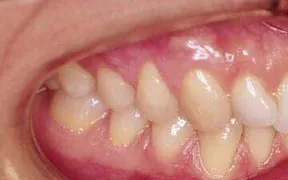

Periodontal Gallery Case 3

This is another case of a gummy smile. The gum tissue covered up too much of the teeth, which caused them to look short.